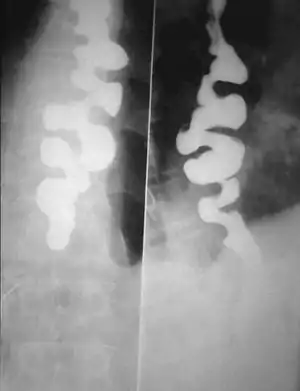

Several radiographic findings are suggestive of DES, such as a "corkscrew esophagus" or "rosary bead esophagus" appearance on barium swallow x-ray, although these findings are not unique to DES.[4]

Upper endoscopy shows corkscrew esophagus

Corkscrew appearance of the esophagus.